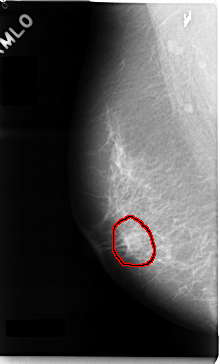

C_0035_1.RIGHT_MLO

FILE: C_0035_1.RIGHT_MLO.OVERLAY

TOTAL_ABNORMALITIES 1

ABNORMALITY 1

LESION_TYPE MASS SHAPE OVAL MARGINS MICROLOBULATED

ASSESSMENT 5

SUBTLETY 5

PATHOLOGY MALIGNANT

TOTAL_OUTLINES 1

BOUNDARY